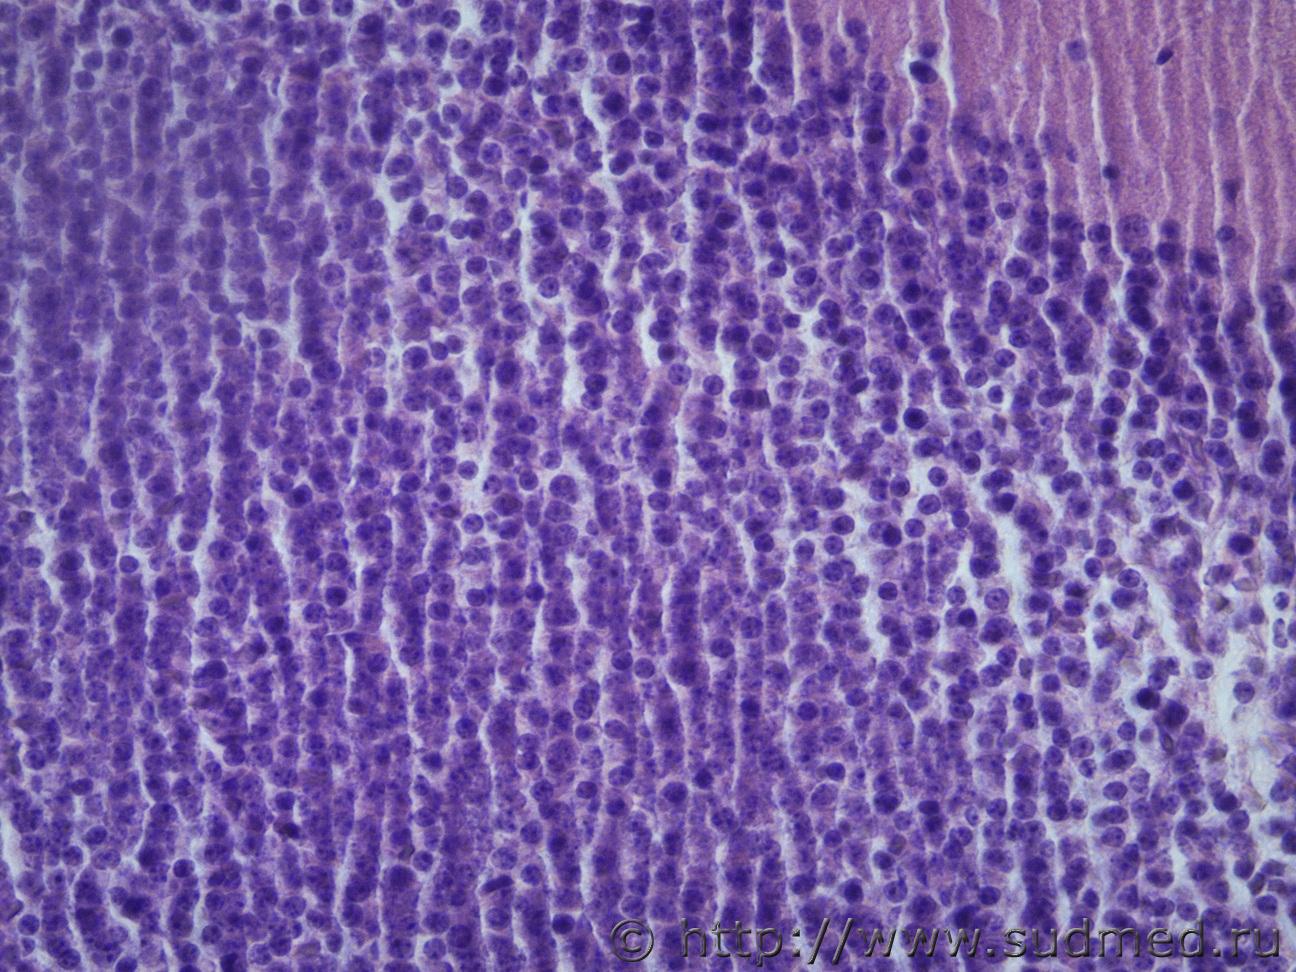

Ув. коллеги, подскажите похоже ли на олигодендроглиому в головном мозге крысы, область гиппокампа? Судебная медицина - Прикрепленное изображение Судебная медицина - Прикрепленное изображениеСудебная медицина - Прикрепленное изображениеСудебная медицина - Прикрепленное изображениеСудебная медицина - Прикрепленное изображение

Отличительной чертой олигодендроглиомы являются петрификаты.Типичным признаком считают "сотовидную" структуру опухолевых клеток,которую им придают светлые перинуклеарные ободки,характерна обильная сеть анастомозирующих капилляров.При анапластической форме наблюдают большую густоту клеток,многочисленные митозы и пролиферацию эндотелия опухолевых сосудов.

А на что это может быть похоже, в норме область гиппокампа у крыс выглядит упорядоченно и более узкой полосой. Вот такСудебная медицина - Прикрепленное изображение

А это ,скорее всего,мозжечок.

Первое фото (сообщение №1), аналогично.

Мозжечка точно не может быть, так как я его при вырезки удалила, срез проходил в средней части головного мозга через височные доли. Мозжечок у крысы выглядит вот так Судебная медицина - Прикрепленное изображение , а это поперечный срез, области гиппокампа, в норме он выглядит вот такСудебная медицина - Прикрепленное изображение ув. в обоих фото х40